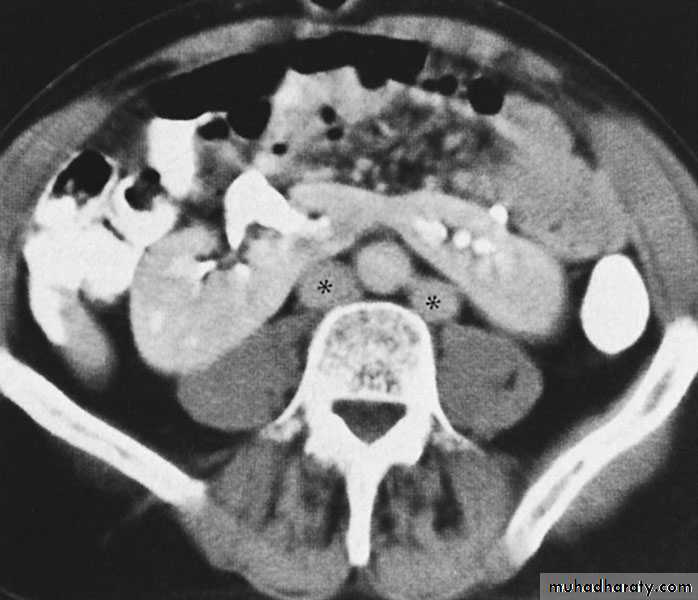

Ureteropelvic Junction (UPJ)(PUJ) Obstruction (stenosis)

The most common cause of significant dilation of the collecting system in the fetal kidney

Boys > Girls

Left-sided lesions predominate

15% bilateral

DIAGNOSIS

U/S: hydronephrosis

IVU: diagnostic , hydronephrosis with

fixed stenotic segment or complete

obstruction

CT scan: hydronephrosis that ends

abruptly